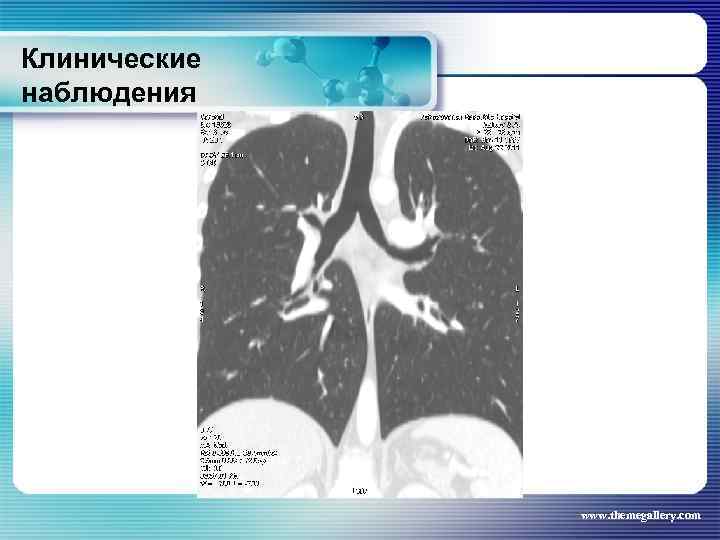

Клинические наблюдения Больной Б. , 1990 г. р. С лета 2008 года увеличены лимфатические узлы на шее. Не обследовался. В течение полугода нарастание слабости, снижение работоспособности, повышение температуры до 38°С, с ознобами и профузными потами. Госпитализирован по месту жительства, а затем в гематологическое отделение. В отделении 02. 2009 г. выполнена биопсия шейного лимфатического узла: лимфома Ходжкина, смешанно-клеточный вариант. При лабораторном исследовании выраженные признаки биологической активности процесса, резко измененные «печеночные» пробы. При лучевом исследовании (рентгенография, СКТ, УЗИ) выявлены признаки поражения внутригрудных, абдоминальных лимфатических узлов, позвонков. www. themegallery. com

Клинические наблюдения Больной Б. , 1990 г. р. С лета 2008 года увеличены лимфатические узлы на шее. Не обследовался. В течение полугода нарастание слабости, снижение работоспособности, повышение температуры до 38°С, с ознобами и профузными потами. Госпитализирован по месту жительства, а затем в гематологическое отделение. В отделении 02. 2009 г. выполнена биопсия шейного лимфатического узла: лимфома Ходжкина, смешанно-клеточный вариант. При лабораторном исследовании выраженные признаки биологической активности процесса, резко измененные «печеночные» пробы. При лучевом исследовании (рентгенография, СКТ, УЗИ) выявлены признаки поражения внутригрудных, абдоминальных лимфатических узлов, позвонков. www. themegallery. com